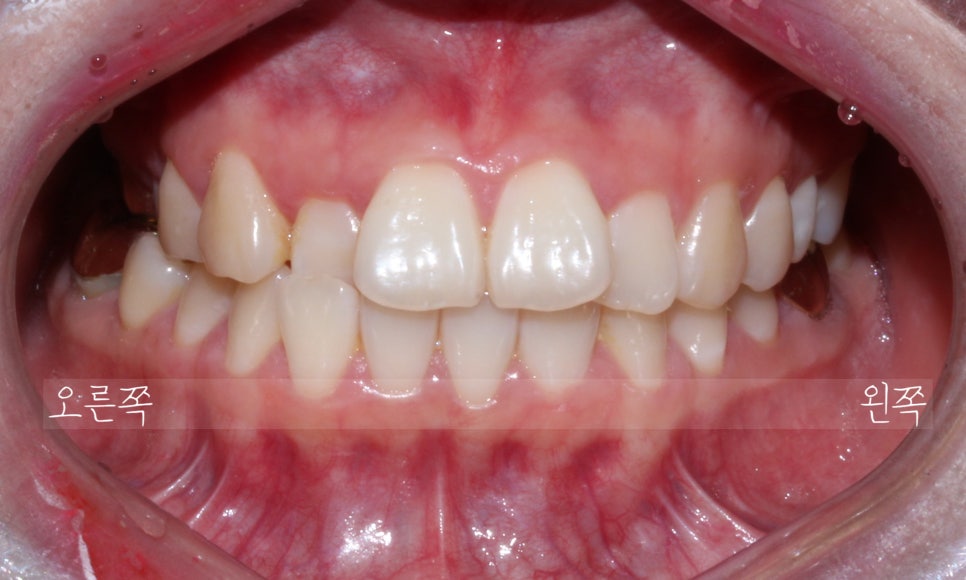

첫 방문

처음 방문 하셨을 때 모습입니다.

오른쪽 두번째 앞니가 거꾸로 물리는 상태이고

(사진상 왼쪽)

윗니가 전체적으로 삐뚤빼뚤한 것이 보입니다.

잘 보이실진 모르겠지만,

우측 구치부는 전반적으로

거꾸로 물리는 양상이 보입니다.